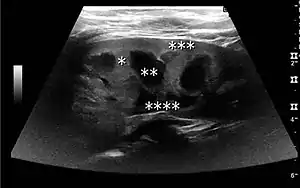

Figure 15. End-stage hydronephrosis with cortical thinning. Measurement of pelvic dilatation on the US image is illustrated by ‘+’ and a dashed line.[1]

Figure 16. Hydronephrosis with dilated anechoic pelvis and calyces, along with cortical atrophy. The width of a calyx is measured on the US image in the longitudinal scan plane, and illustrated by ‘+’ and a dashed line.[1]

Figure 17. Same patient as in Figure 16 with measurement of the pelvis dilation in the transverse scan plane illustrated on the US image with ‘+’ and a dashed line.[1]

The hydronephrosis is typically graded visually and can be divided into five categories going from a slight expansion of the renal pelvis to end-stage hydronephrosis with cortical thinning (Figure 15). The evaluation of hydronephrosis can also include measures of calyces at the level of the neck in the longitudinal scan plane, of the dilated renal pelvis in the transverse scan plane and the cortical thickness, as explained previously (Figure 16 and Figure 17).[1]